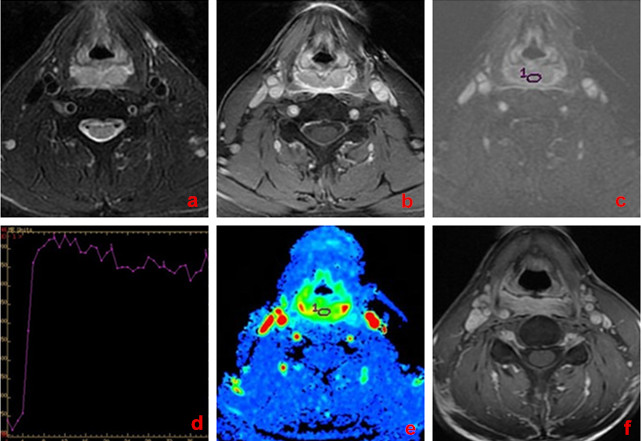

Figure 1: A 58-year-old man with larynx carcinoma, good response to chemo-radiotherapy. a. Transverse T1-weighted imaging. b. Transverse T2-weighted imaging. c. DCE-MRI map. d. TIC map. e.The MSI map, MSI value was calculated as 168.74. f. Transverse T1-weighted enhancement imaging show that tumor mass was reduced obviously ( > 50% reduction) after treatment.

54 of 62 patients (87.1%) were categorized into the responder group (CR, n = 28; PR, n = 26; Figure 1) whereas the other 8 were considered non-responders (SD, n = 8; Figure 2) at the end of treatment. For primary tumors, the pretreatment TTP, MSI, MSD, and PEI for responders were 80.96±17.59seconds, 227.49±70.58, 130.69±126.99, and 198.39±92.18, respectively; for non-responders they were 85.06 ± 22.05 seconds, 126.92±45.15, 73.32±64.33, and 133.76±57.05, respectively (P = 0.401, 0.000, 0.025, and 0.001, respectively, Table 2).